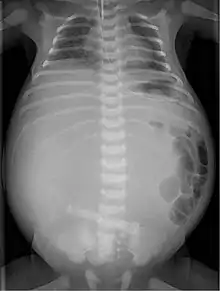

Radiograph with double bubble sign indicating duodenal atresia

If not diagnosed in utero, infants with intestinal atresia are typically diagnosed at day 1 or day 2 after presenting with eating problems, vomiting, and/or failure to have a bowel movement.[3] Diagnosis can be confirmed with an X-ray, and typically followed with an upper gastrointestinal series, lower gastrointestinal series, and ultrasound.[5][3]